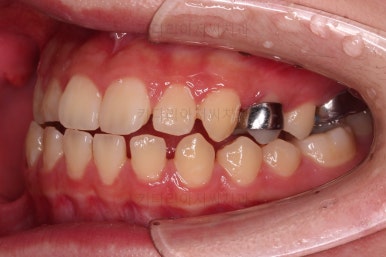

악궁확장 이 후 브라켓을 부착합니다.

이번 환자분이 선택하신 장치는 엠파워 클리어라고 하는 자가결찰 세라믹 장치인데요.

철사를 스스로(자가) 묶을 수(결찰) 있는 뚜껑이 달린 세라믹 성분의 장치입니다.

대표적인 장치가 클리피씨 장치이며 클리피는 일본회사, 동래교정치과 키다리아저씨치과가 쓰는 엠파워는 미국회사라는 차이가 있고 큰 틀에서는 동일한 계열의 장치입니다.